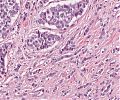

A62 Plattenepithelkarzinom (Zunge)

Gut differenzierte, epidermoide Tumorzellen mit Verhornung

-

A62 Plattenepithelkarzinom (Zunge)

Epidermoid differenzierte Tumorformationen mit Verhornung, gut differenziert

Plattenepithel_CA_Zunge1_A62.png

Invasiv wachsendes Plattenepithelkarzinom mit variabler extrazellulärer Verhornung.

Plattenepithel_CA_Zunge_A62.png

Mäßige Kernpleomorphie der Tumorzellen. Zentral Ausildung einer Hornperle.